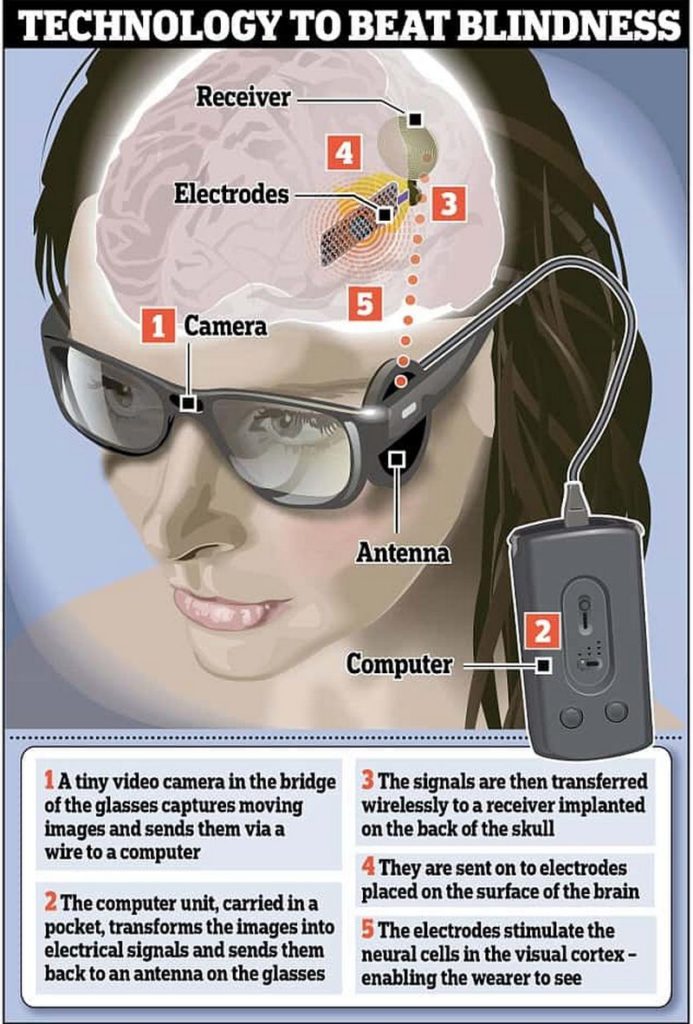

Nader Pouratian презентував проміжні результати раннього дослідження системи кортикального зорового протезу Orion (Second Sight Medical Products). Імплантат було встановлено шести пацієнтам. Він напряму стимулює зорову кору, оминаючи очі та зорові шляхи. Сам імплантат отримує сигнал від спеціальної камери, що розташований на окулярах, які носить пацієнт. Камера фіксує зображення в режимі реального часу, які обробляються VPU, а потім перетворюються на патерни стимуляції, які через бездротовий зв’язок передаються до електродів, імплантованих в зорову кору. В дослідження були включені пацієнти, які раніше мали здатність бачити, але втратили зір через причини, які не включали ураження зорової кори.

Принцип роботи системи Argus II